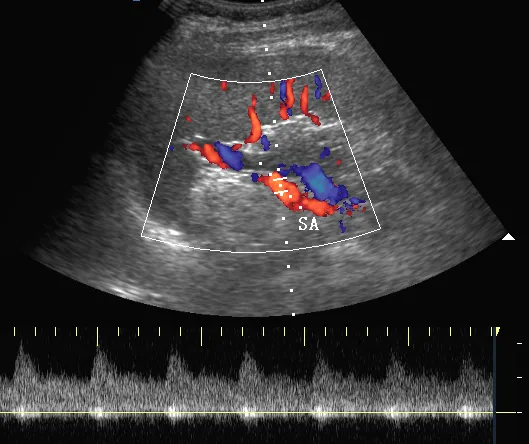

彩色多普勒,正常脾脏,显示脾门处红色的脾动脉(SA)和蓝色的脾静脉(SV) 。

脉冲多普勒,正常脾脏,显示脾动脉搏动性血流曲线(图1,SA)和脾静脉连续性血流曲线(图2,SV)。